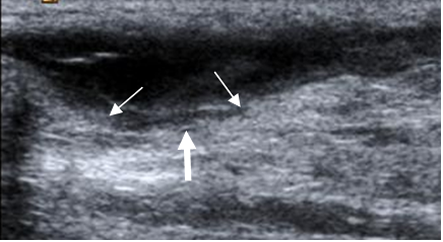

Fig 78. Ruptura tendinosa.

Ecografía vista sagital. Ruptura completa del aquiles, con líquido y tejido inflamatorio,

(Flecha gruesa), entre los extremos (Flechas delgadas).